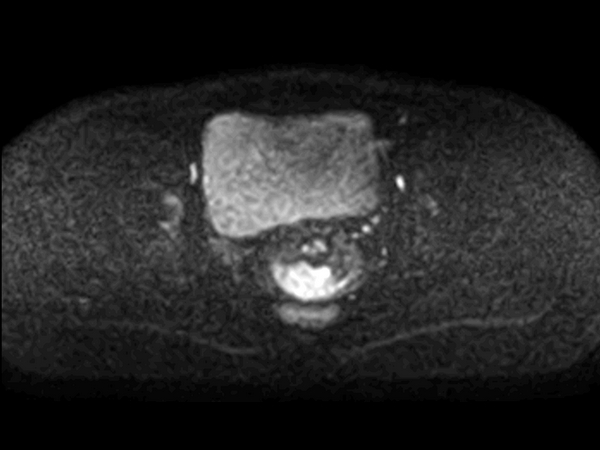

Axial DWI SPAIR (b800) mid

-